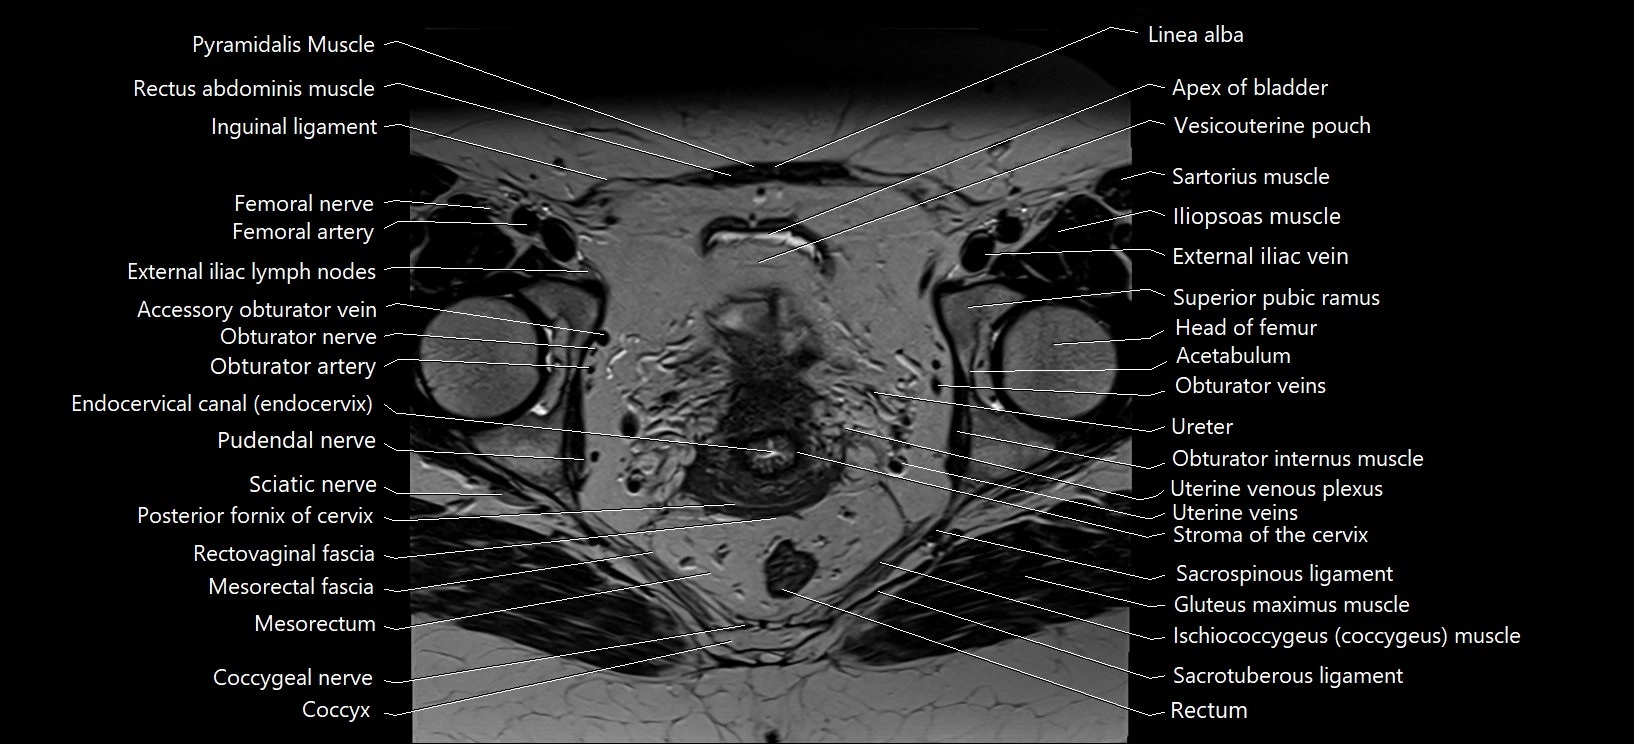

- Accessory obturator vein

- Acetabulum

- Cervix of uterus

- Coccygeal nerve

- Coccyx

- Endocervical canal

- External iliac lymph nodes

- External iliac vein

- External os of the cervix

- Femoral nerve

- Gluteus maximus muscle

- Head of femur

- Iliopsoas muscle

- Inguinal ligament

- Linea alba

- Mesorectal fascia

- Mesorectum

- Obturator artery

- Obturator externus muscle

- Obturator internus muscle

- Obturator nerve

- Obturator vein

- Obturator veins

- Pectineus muscle

- Pubic symphysis

- Pudendal nerve

- Pyramidal muscle (pyramidalis muscle)

- Rectovaginal septum (rectovaginal fascia)

- Rectum

- Rectus femoris muscle

- Sacrospinous ligament

- Sacrotuberous ligament

- Sartorius muscle

- Sciatic nerve

- Stroma of the cervix

- Superficial inguinal lymph nodes

- Superior pubic ramus

- Uterine veins

- Uterine venous plexus